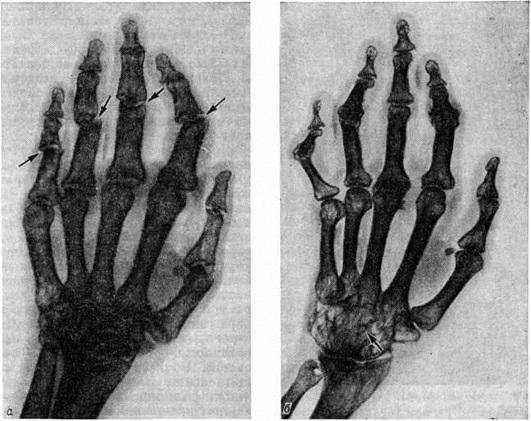

Рентгенодиагностика. В задачи рентгенодиагностики входит, помимо распознавания болезни, также оценка характера, тяжести и распространённости изменений костно-суставного аппарата, определение стадии, а при повторных исследованиях оценка эволюции заболевания. Наиболее распространённой методикой рентгенологическое исследования является стандартная рентгенография суставов. Более детальное изображение структуры кости можно получить, используя безэкранную рентгенографию. Томография (смотри полный свод знаний) при Ревматоидный артрит применяется крайне редко и имеет лишь вспомогательное значение. Поскольку наиболее характерные для Ревматоидный артрит рентгенологическое изменения обнаруживаются у взрослых в кистях и дистальных отделах стоп, а у детей, кроме того, и в шейном отделе позвоночника, эти области исследуют в первую очередь. Динамика рентгенологическое изменений при Ревматоидный артрит отличается медленным темпом, что делает излишним частое повторение исследования.

Продолжительность рентгенонегативного периода при Ревматоидный артрит значительно варьирует и чаще всего составляет от нескольких недель до 1—2 месяцев Ревматоидному артриту свойственны симметричность изменений суставов и склонность этих изменений к прогрессированию. Прогрессируют выявляемые рентгенологические изменения неравномерно, ускоряясь при обострениях болезни и замедляясь, вплоть до полной стабилизации, в периоды ремиссий. У ряда пациентов не отмечается корреляции между клинические, течением болезни и прогрессированием рентгенологическое изменений, в частности рентгенологическое картина может ухудшаться при отсутствии клинические, признаков активности ревматоидного артрита.

При Ревматоидный артрит обнаруживаются разнообразные рентгенологическое симптомы, ни один из которых нельзя считать патогномоничным. Ранние рентгенологическое изменения при Ревматоидный артрит являются неспецифичными, так как свойственны всем артритам (смотри полный свод знаний), и характеризуются утолщением мягких тканей в области поражённых суставов и околосуставным остеопорозом (смотри полный свод знаний). На ранней стадии более чем у половины больных Ревматоидный артрит отмечаются также кистовидные просветления в ближайших к суставам участках костей.

В дальнейшем присоединяется сужение суставных щелей, эрозии костей, подвывихи и вывихи (рисунок 7, 8). Часто на фоне описанных изменений на краях суставных поверхностей формируются остеофиты — проявление вторичного артроза. Тяжёлое ревматоидное поражение суставов может приводить к их анкилозированию; в случаях особо неблагоприятного течения возможен остеолиз ближайших к суставам отделов костей (рисунок 9). Как редкие рентгенологическое симптомы встречаются периоститы (смотри полный свод знаний), асептические остеонекрозы (смотри полный свод знаний: Остеохондропатия).

На основании рентгенологическое изменений суставов выделяют стадии Ревматоидный артрит Из многочисленных схем наиболее известна схема Стайнброккера, согласно которой выделяют 4 стадии ревматоидного артрита. К 1-й стадии относят случаи с околосуставным остеопорозом (смотри полный свод знаний), но без сужения суставных щелей и эрозии костей. Если к остеопорозу присоединяется сужение суставных щелей, то это соответствует 2-й стадии. Наличие эрозий костей указывает на 3-ю стадию, а костного анкилоза — на 4-ю стадию. Ларсен (A. Larsen, 1974) предложил более детализированную оценку, выделив 6 стадий, и дал для каждого сустава отдельную схему, отражающую местные особенности проявлений Ревматоидный артрит